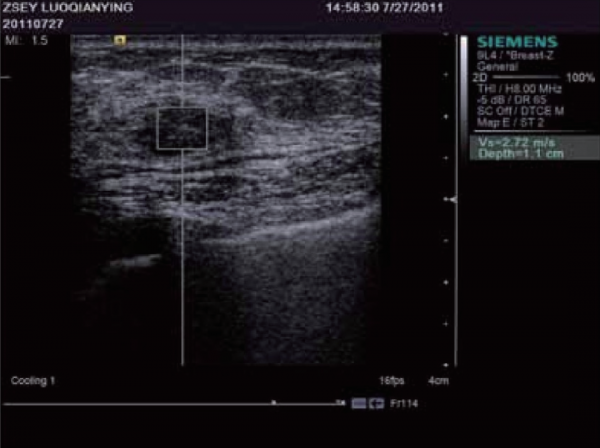

諧波運動成像最早由Maleke等人提出。透過探頭產生的超聲波對組織施加週期性的聲輻射力,使組織產生諧波運動。透過獲取組織被激發前後的B超影象並對其進行運動估計,可以間接反映組織的彈性狀況。該方法可以準確反映深部組織的區域性彈性狀況,但由於需要在激發訊號的同時監測組織的運動,因而採集到的B超訊號容易受到激發訊號的嚴重干擾,這是該成像方法迄今為止尚未得到完美解決的主要問題。當聲輻射力作用在組織上時會激發出剪下波,剪下波彈性成像正是透過檢測這一剪下波的傳播來達到成像的目的,最早由美國學者Sarvazyan和Emelianov提出。他們利用高強度聚焦超聲探頭產生聲輻射力,在人體組織中產生了明顯的剪下波,並運用磁共振成像方法監測該剪下波的傳播情況。由於剪下波速與人體組織的粘彈特性緊密相關,因此透過檢測剪下波的傳播速度等引數可以獲取組織的彈性資訊。圖12顯示了某一慢性肝病患者的肝臟彈性成像圖。聲輻射力脈衝成像技術最早由杜克大學的學者Nightingale等人提出,該方法透過高能聚焦超聲探頭在區域性組織中產生短暫的高強度聲輻射力,從而推動組織產生一定的應變,再透過追蹤這些微小應變和剪下波的傳播來判斷組織的粘彈特性。研究人員發現,組織對於脈衝聲輻射力的瞬態響應直接相關於區域性區域的硬度大小,而透過求解亥姆霍茲方程的反問題方法可以量化組織中剪下波的波速。Nightingale等透過詳細的數值模擬和體模研究證實了聲輻射力脈衝成像的可行性,並得到了與傳統B超影象相比更高的對比度和分辨力。如今的聲輻射力脈衝成像已在臨床上具備多種臟器檢查的能力,圖13顯示了某位良性纖維瘤患者的乳腺聲輻射力脈衝成像圖。

圖13 乳腺良性纖維瘤患者的聲輻射力脈衝成像圖